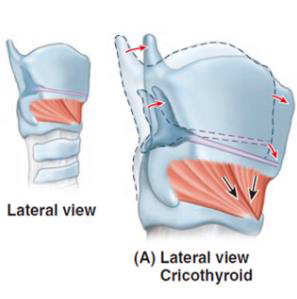

Motor: External laryngeal n.

- Cricothyroid m.

- Cricothyroid m.